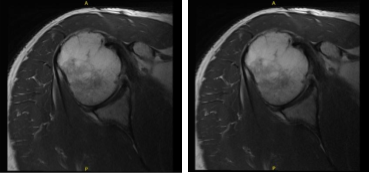

An MRI result was presented which showed biceps tenodesis and possible tear in the rotator cuff. Evidence of prior rotator cuff repair with suture anchor in the greater tuberosity. However, findings compatible with a recurrent tear of the supraspinatus at least moderate severity.

Low-grade partial thickness tear of the subscapularis tendon. Biceps tendinosis and tenosynovitis without tears. Findings suggesting adhesive capsulitis. Small tear at the base of the anterior labrum. Mild bursitis.

MRI-3T Right Shoulder non-contrast